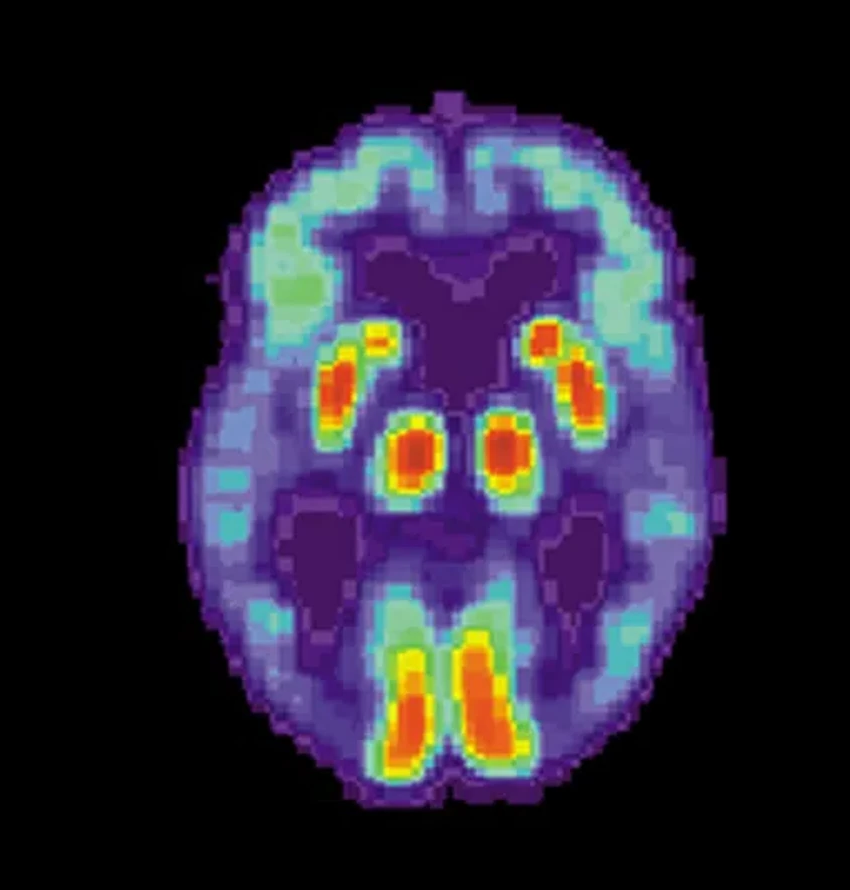

Анализ МРТ-снимков огромной армии добровольцев выявил пять чётких паттернов, по которым мозг уменьшается с годами или под натиском нейродегенеративных болезней. Эти паттерны не просто абстракция — они напрямую связаны с факторами риска, которые частично в нашей власти. Работа, занявшая у команды около восьми лет, опубликована в авторитетном Nature Medicine.

Три из пяти выявленных паттернов оказались тесно связаны с деменцией и её предвестником — лёгкими когнитивными нарушениями. Но что ещё важнее — эти модели оказались предсказательными. «Если вы хотите спрогнозировать переход от нормы к лёгким нарушениям, одна из моделей даёт самый точный ответ», — объясняет Давацикос. Другие паттерны были ассоциированы с болезнями Паркинсона и Альцгеймера. А комбинация трёх определённых моделей и вовсе указывала на резко повышенный риск смерти. Сильно, правда?

Учёные также обнаружили чёткие связи между каждым «узором старения» и конкретными факторами: злоупотреблением алкоголем, курением, определёнными генетическими маркерами и биохимическими показателями крови. Давацикос полагает, что это отражает простую истину: общее здоровье тела неотделимо от здоровья мозга. Повреждение других органов обязательно аукнется и в черепной коробке.